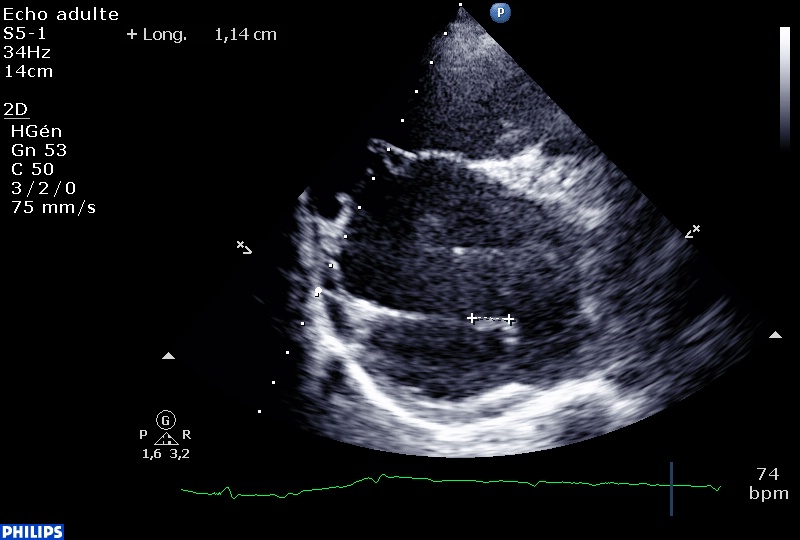

Dans la même semaine, deux vieilles dames en insuffisance cardiaque à prédominance droite, en fibrillation auriculaire chronique et présentant une HTAP importante ont des images échographiques étranges…

La premières sur la valve aortique : plusieurs éléments filamenteux, fins, mobiles, sur le versant ventriculaire et sur le versant aortique, sans le moindre contexte infectieux, et sans dysfonction de la valve.

En grand axe:

Le strand est défini comme un élément filamenteux, de moins de 1 mm d’épaisseur, plus généralement sur la valve mitrale que sur la valve aortique, plutôt sur le versant ventriculaire de la valve aortique et sur le versant auriculaire de la mitrale. Globalement, il semble qu’il y ait un lien entre la présence d’un stand et le risque d’Accident Vasculaire Cérébral chez le patient « tout venant ».